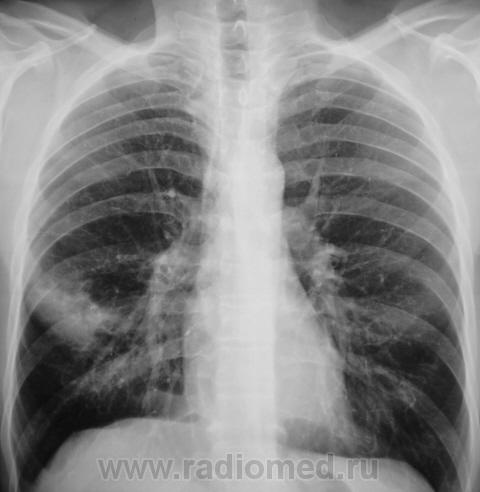

Первое исследование.